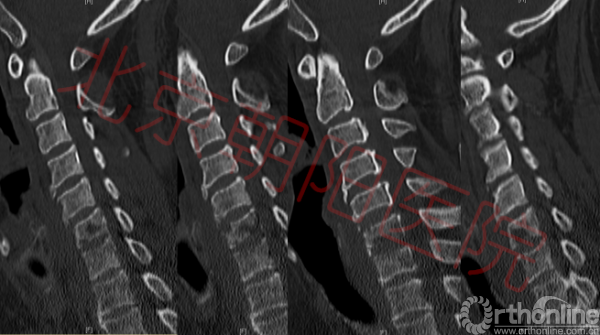

入院后常规给予患者营养神经等治疗,患者第二天出现体温升高,最高达38.5℃,同时血常规回报:白细胞12.81*10^9,中性粒细胞80.5%,淋巴细胞12.7%;ESR:80mm/h(正常值2-15);CRP:1.19ng/dl(正常值0-0.8)。降钙素原:提示基本无细菌感染或是细菌感染恢复期;考虑患者存在感染!立即给予患者头孢西丁钠抗感染治疗。复查胸椎核磁、颈椎核磁、颈椎CT(如图2,3);腰椎穿刺取脑脊液,脑脊液压力高;完善脑脊液常规、生化、免疫及结核相关检查,结合患者症状、病史、体征及辅助检查,排除肿瘤、免疫、结核、真菌感染等疾病,考虑诊断为化脓性颈椎炎,硬膜外脓肿,颈椎病,不完全性瘫痪,II型糖尿病。

图2:如图可见脊髓多节段受压,C6、C7椎体及椎间盘高信号,C6-C7椎体后方可见高密度影,C5-C8椎体前方高密度影。脊髓内可见高信号区域

图3:如图可见C6、C7椎体不同程度骨质破坏